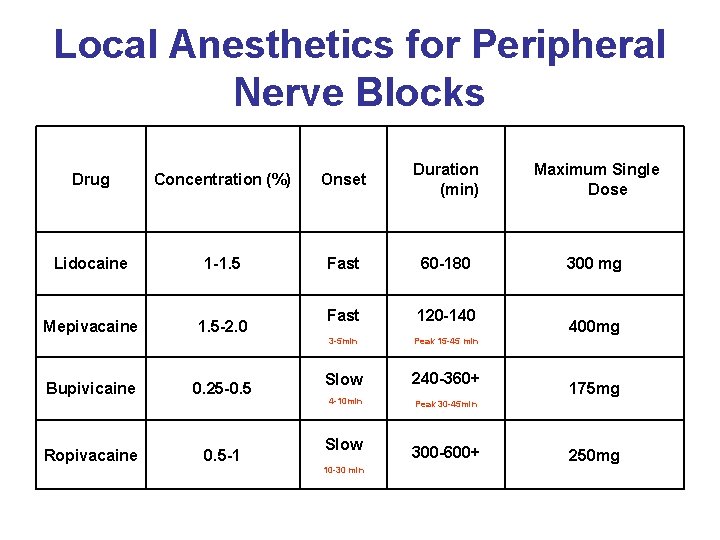

Local Anesthetics for Peripheral Nerve Blocks Drug Concentration (%) Onset Duration (min) Maximum Single Dose Lidocaine 1 -1. 5 Fast 60 -180 300 mg Mepivacaine 1. 5 -2. 0 Fast 120 -140 3 -5 min Peak 15 -45 min Slow 240 -360+ 4 -10 min Peak 30 -45 min Bupivicaine Ropivacaine 0. 25 -0. 5 -1 Slow 10 -30 min 300 -600+ 400 mg 175 mg 250 mg